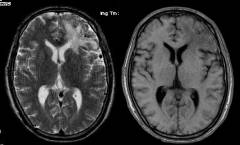

5、頭顱MRI或MRA可見病變區無信號迂曲成團血管影,MRA可見供血動脈、畸形血管團及引流靜脈。

⑤磁共振成像(MRI)。由於流空效應,大多數動靜脈畸形呈無信號的紆曲成團的血管影,在MR上呈黑色。對腦血管造影不能顯示的隱匿性動靜脈畸形MR及CT可互相補充予以確診。